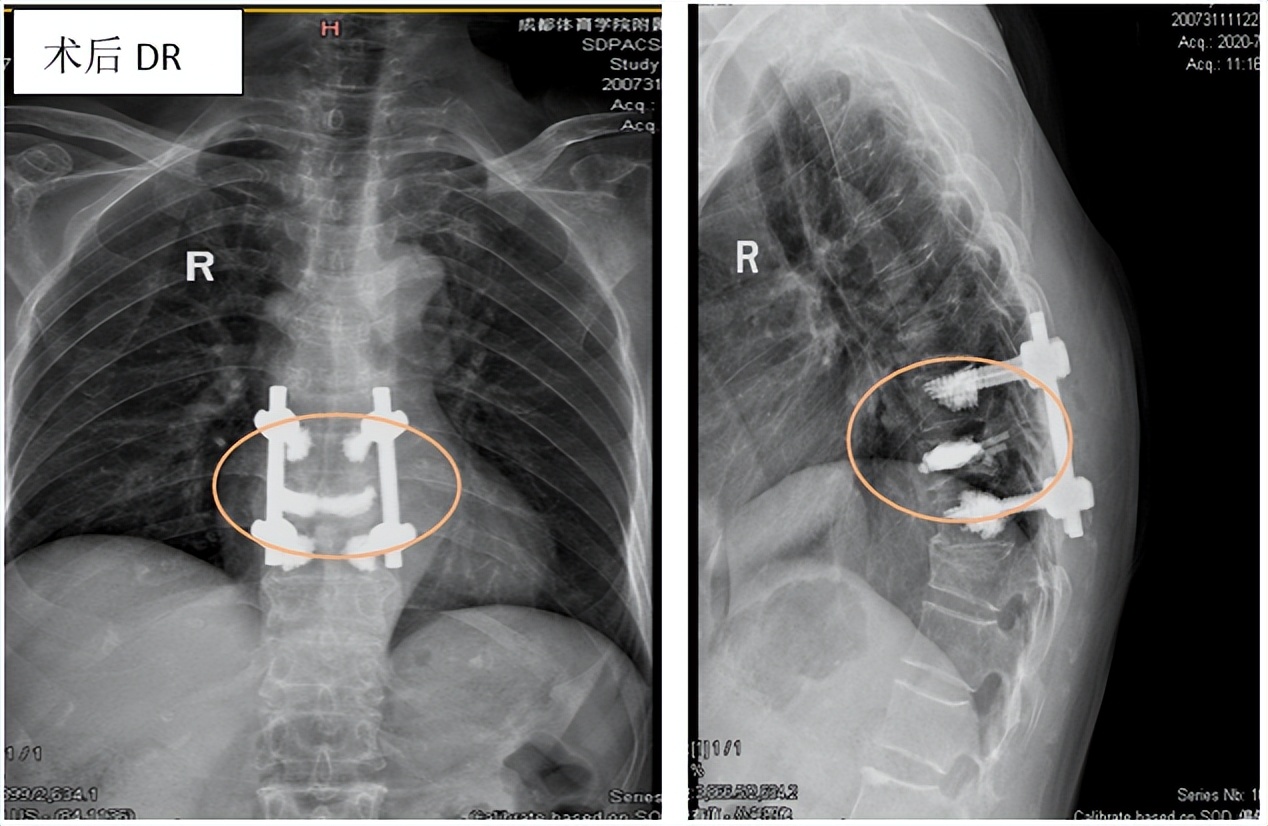

※开放手术

椎弓根钉-棒系统内固定 :主要适用于严重后凸畸形需要截除椎骨矫正,椎体后缘骨块碎裂后压迫脊髓,神经损伤症状、体征显著,以及不稳定椎体骨折患者。

※开放手术治疗 :切开复位、经椎弓根螺钉内固定术,复位效果较好,可以矫正后凸畸形并增强脊柱稳定性。但手术创伤相对较大,恢复相对较慢。